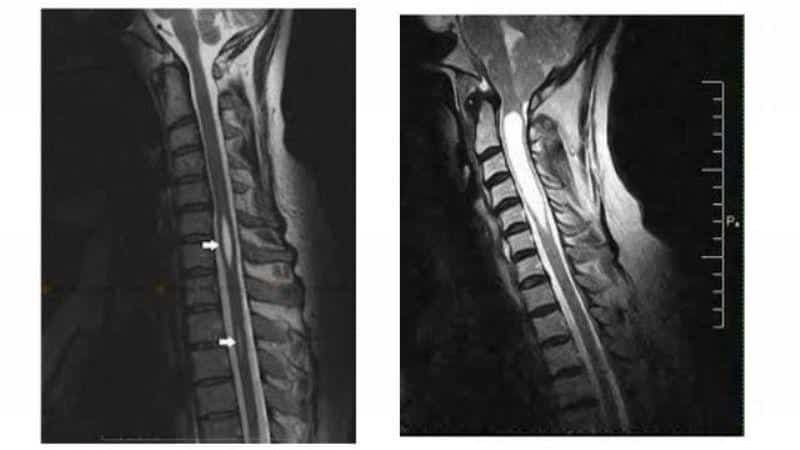

Для установления точного диагноза необходимо обратиться к врачу-неврологу. Этот специалист основывает свои выводы на данных, полученных с помощью компьютерной и магнитно-резонансной томографии. Исследованию могут подвергаться различные отделы позвоночника: грудной, шейный, а в редких случаях и поясничный.

Диагностика сирингомиелии обычно включает в себя магнитно-резонансную томографию (МРТ), которая позволяет визуализировать наличие кист в спинном мозге. Также могут быть проведены неврологические тесты для оценки функции нервной системы.